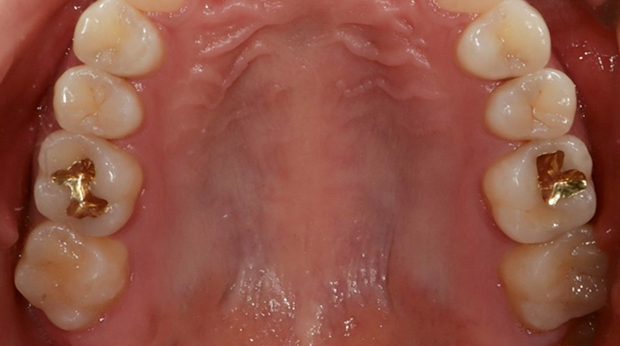

구강외과 진료

라미네이트

고난도 수술 진료